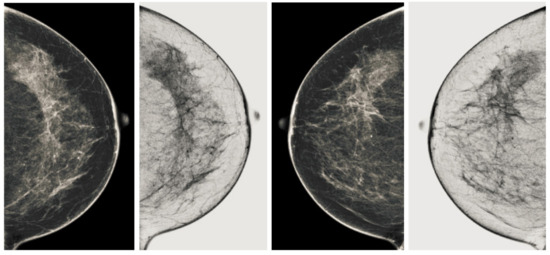

Computerized analysis of mammography is also challenging because one of the most important challenges is observing the pectoral muscles. The geometric shape of the pectoral muscles and their location depend on the mammographic images’ specific view [12,13]. There are two types of mammographic image views: the carnio-caudal (CC) view and the mediolateral oblique (MLO) view, and these views are shown in the Figure 1. The pectoral muscle on the CC view is semi-elliptical along the breast wall. In contrast, the MLO view covers most of the upper mammogram coverage and roughly corresponds to the overlapping right-angled triangle, as shown in Figure 1. Due to their appearance, both views suffered from low contrast, which made it difficult to see cancerous areas in some cases. Image enhancement requires correct observation and helps segment abnormal regions for disease classification. The quality of mammography images in terms of noise reduction and contrast enhancement is improved by using the image enhancement technique. The main purpose of implementing the image enhancement technique is to help the computerized breast cancer detection system to detect mammographic lesions with poor visibility and improve low contrast. Low contrast regions with small abnormalities are mostly hidden in the tissue of mammogram images, which makes it challenging to analyze the abnormal region, and also provides false detection.

Figure 1.

Representation of standard mammography views. The figure (a) represents the CC view of the right and left breast, and the figure (b) represents the MLO view of the right and left breast.